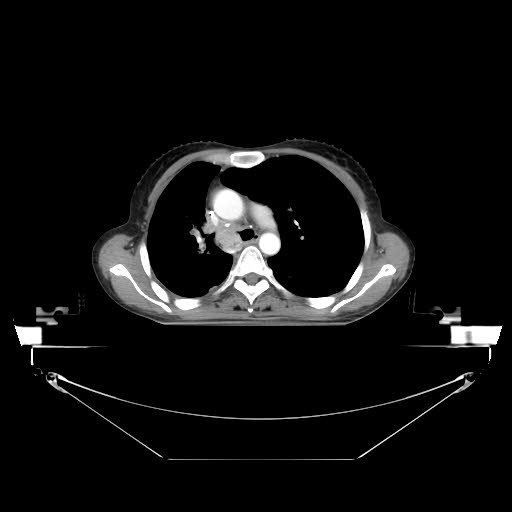

然而看着病人绝望的眼神,以及家属无能为力的失落,作为医者,内心的痛苦不亚于输了一场战争。刘佳宏副主任认真核对患者既往检查资料,一一对比,同时结合本院CT图像进行认真分析,认为病人可行“肺动脉部分栓塞止血”,在取得家属的认同与理解的前提下,手术日程确定了下来。

虽然术前对于手术的困难程度有了充分的准备,但是手术进行中才发现,患者右侧肺部因为长期肿瘤组织的异常供血,以及已行介入手术治疗,导致部分异常血管再通以及侧支循环建立,血管的扭曲程度,以及正常解剖结构大部分变形,对于目标血管的追寻困难重重。

通常情况下,右肺支气管动脉常开口于胸主动脉,反复造影,均未见支气管动脉显影。初步考虑有支气管动脉异位,上行至右侧锁骨下动脉,“冒烟”发现胸廓内动脉一分支明显增粗,进入肺内,同时远端可见造影剂外溢,遂行“灌注+栓塞”术,直至血流中断。

然而结合CT图像考虑,主要出血点不在此处,那么罪魁元凶到底在哪里呢?众所知周,支气管动脉开口异常的比例极其高,可开口于胸主动脉、膈动脉、胸廓内动脉、甲状腺颈干等等。

手术前